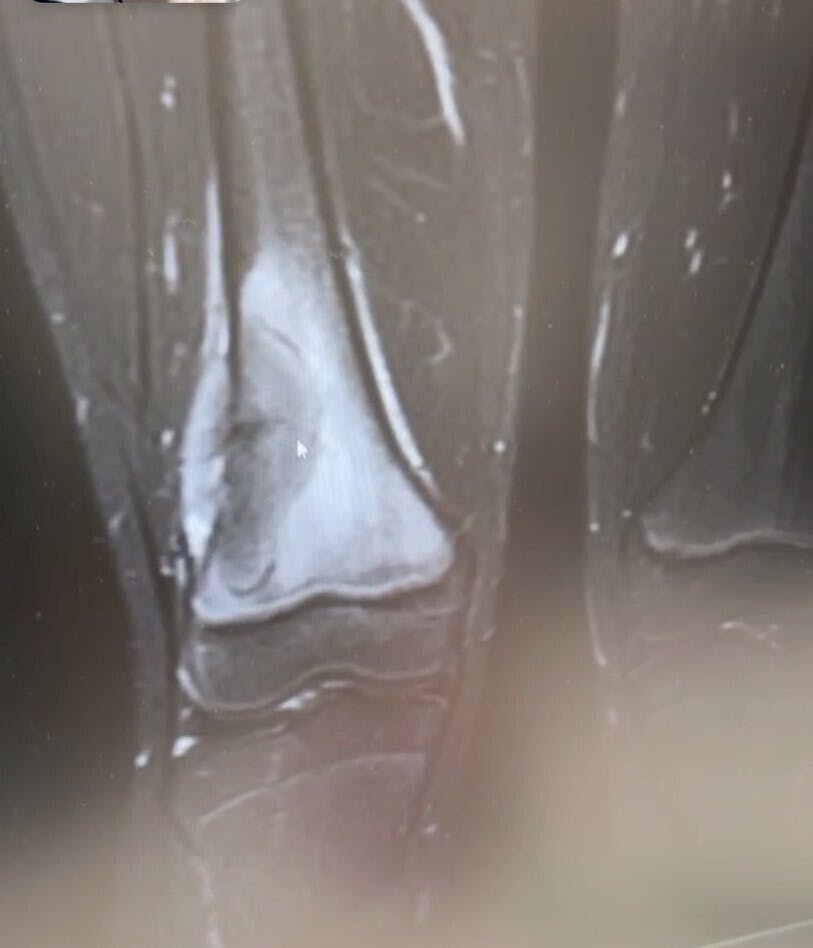

これも念のために今度は専門の病院でMRIを撮りましょうとなった

2024年12月23日 専門の病院でMRIを撮る

実際のレントゲン写真

ここで改めて『骨肉腫』ってどんな病気?

骨肉腫は成長期である10歳代の四肢、特に膝関節周辺に好発する悪性腫瘍です。 原因は不明ですが、成長期である10歳代に最も多く全体の60%を占めることから、骨成長の速さと骨肉腫の発症の関連性が提唱されています。 発症部位は約70%が膝関節周囲で大腿骨遠位端、脛骨近位骨幹端、次に10%が上腕骨近位骨幹端です。